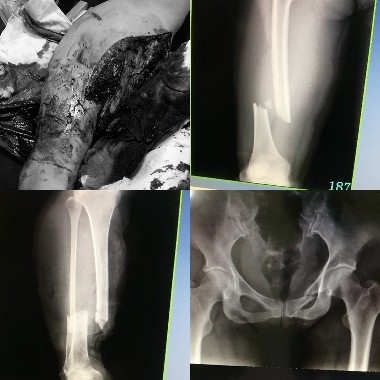

趙女士入院后,神志淡漠、血壓低、生命體征不穩(wěn),休克。右大腿骨折、右小腿皮膚軟組織大面積創(chuàng)傷,小腿不完全離斷,足部無(wú)血運(yùn)。因右下肢多發(fā)骨折合并血管損傷,出血量達(dá)到2200~3000ml,患者生命垂危。經(jīng) X線(xiàn)片檢查顯示"右脛腓骨、右股骨干骨折、右坐骨支骨折",急診科立即予以右下肢傷口加壓包扎止血、補(bǔ)液治療。搶救中時(shí)間就是生命,考慮到患者傷情較重,若不及時(shí)手術(shù)傷情惡化將會(huì)造成肢體截肢,甚至危急生命。骨一科馬秀軍主任、喬剛醫(yī)生馬上組織科內(nèi)醫(yī)護(hù)人員進(jìn)行搶救,急查血常規(guī)、肝腎功能、電解質(zhì)、凝血功能了解患者基本情況后,在全麻下行股動(dòng)靜脈、脛前動(dòng)靜脈吻合大小腿骨折鋼板內(nèi)固定術(shù),術(shù)中清除積血約1500ml,輸血2400ml。由于患者多發(fā)骨折創(chuàng)面大,失血量大,病情重,為搶救帶來(lái)極大困難。手術(shù)歷經(jīng)10小時(shí)后順利結(jié)束,術(shù)后患者血壓回升,肢體血供恢復(fù),已轉(zhuǎn)入ICU繼續(xù)治療。